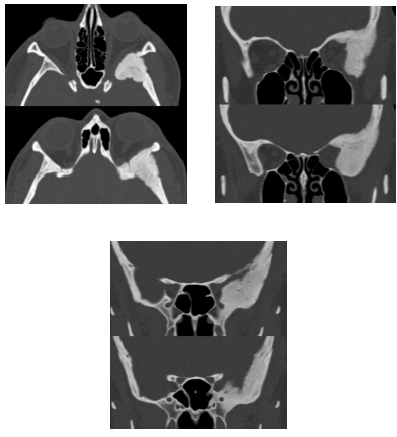

Paciente com 44 anos de idade, do sexo feminino, apresenta exoftalmia à esquerda de causa desconhecida, sem outras queixas ou outras patologias conhecidas. A seguir são mostradas imagens obtidas pela tomografia computadorizada realizada pela paciente.

Com relação à patologia apresentada nos exames, julgue o item seguinte.

Além da modalidade esclerótica, essa lesão pode ainda apresentar aspecto em vidro fosco, cístico, ou em “bolhas de sabão”.

A cintilografia óssea não demonstrará captação nas áreas afetadas pela doença, de modo que não auxiliaria na avaliação da sua distribuição e atividade, embora colaborasse no diagnóstico diferencial com doença de Paget.

A referida lesão determina densificação e importante aumento de resistência do osso acometido, além de comumente expandir o osso comprimindo às estruturas adjacentes, sem, contudo, invadi-las.

A forma poliostótica dessa doença, em associação com lesões cutâneas tipo “café-com-leite” e puberdade precoce, sugeriria a possibilidade de síndrome de Von Recklinghausen.

O quadro é típico de displasia fibrosa esclerótica, havendo a possibilidade de meningioma em placa como importante diagnóstico diferencial.